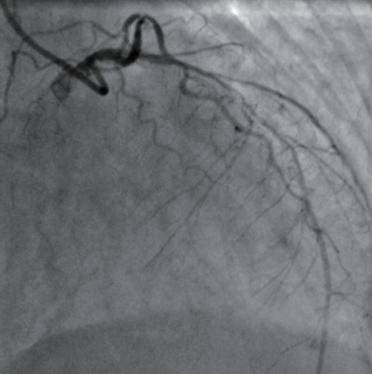

(4)将斑块磨通后选择型号合适的支架覆盖病变部位,再予高压球囊充分扩张支架,如造影显示支架与血管壁贴合紧密(图1-3-3),血管腔内血流通畅,血管壁完好,无造影剂滞留、渗出,冠状动脉各分支完好,患者不适症状减轻或消失,则撤出各导丝及导管,予桡动脉压迫止血器压迫穿刺口,手术结束,护送患者安返病房。

图1-3-3 旋磨术后冠状动脉支架置入后的造影